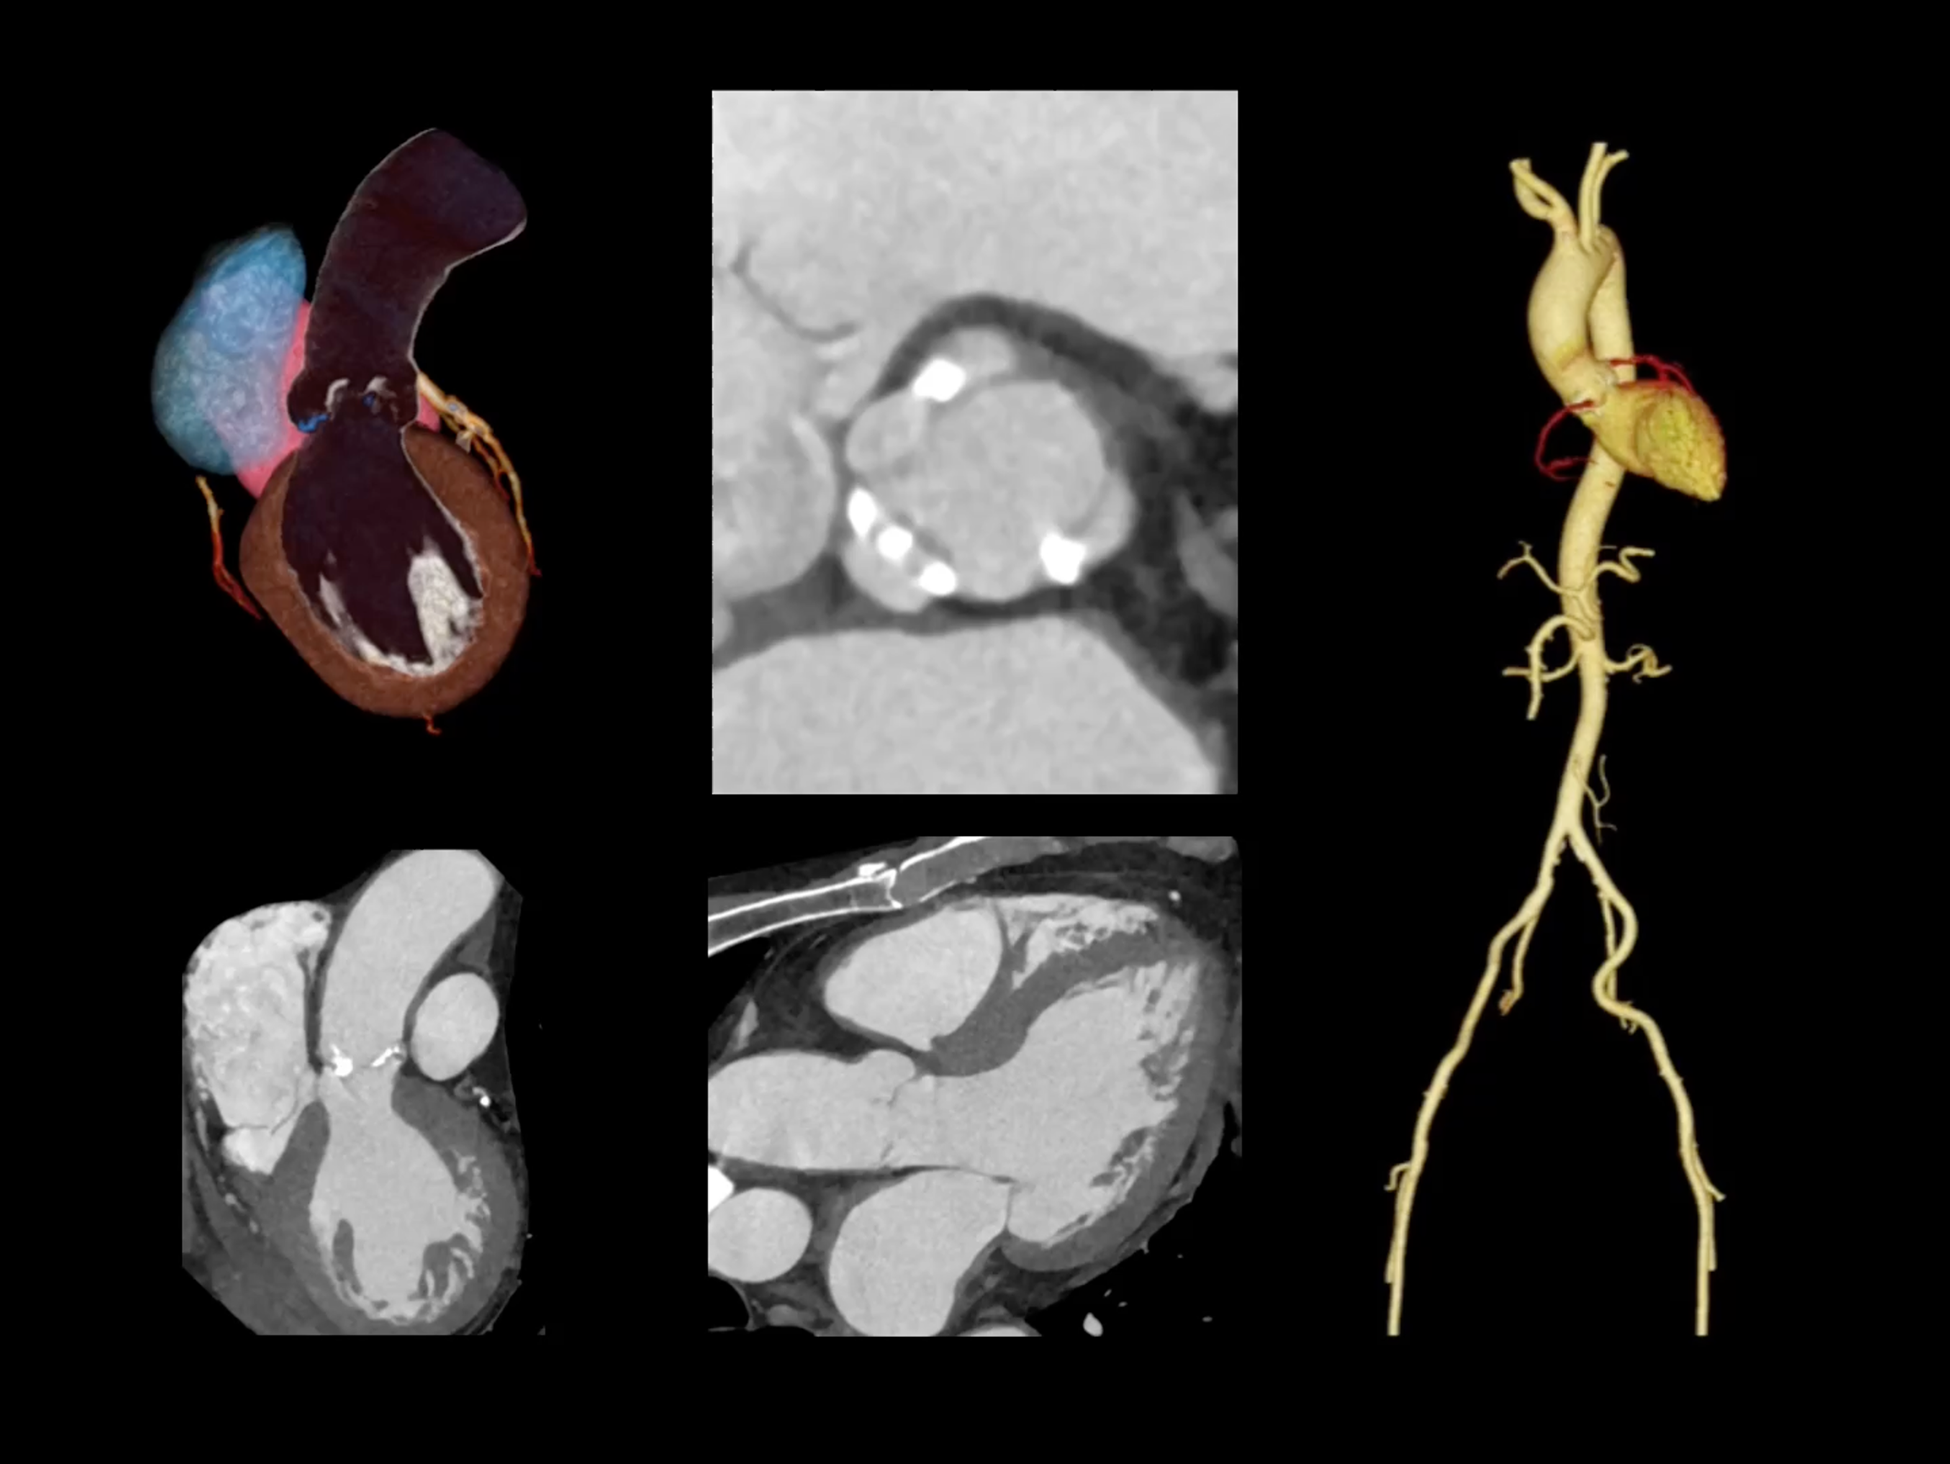

全时心脏

uCT SiriuX® 挑战心脏成像时间分辨率的极限,精准捕捉心脏全周期的动态变化。无论静态解剖形态,还是动态功能表现,都能清晰呈现,让心脏不再是“定格”的器官,而成为可视的生命律动。

心脏成像,自由掌控

uCT SiriuX® 以 8ms 全心等效时间分辨率与16cm宽体覆盖,突破传统心脏成像局限,完整呈现搏动中的心脏结构与动态功能;配合无心电门控扫描与智能化工作流,更使心脏检查摆脱心率、配合度与操作复杂度的束缚,实现真正自由从容的成像体验,为临床功能评估提供更深层依据。

全心4D电影成像

提供全心动周期内多个时相的清晰结构成像信息,动态展示心脏结构运动变化。

全心全时相高清成像

单心动周期内的任意时相获取高质量的冠脉CTA图像,确保稳定的心脏成像效果。

一站式心脏多维成像

一次对比剂注射可同时获取冠脉CTA、心肌灌注和心肌延迟强化等多维图像信息。

全域能谱

uCT SiriuX® 依托16cm超宽探测器与双源能谱技术,实现真正意义上的全身高清能谱成像。单次扫描同步获取灌注、能谱等多维定量参数,精准解析组织特性与病灶成分,为临床决策提供更深层次的诊断依据。